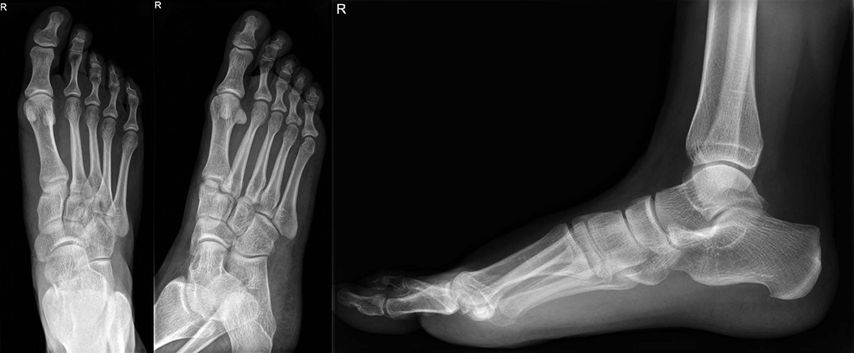

Die bildgebende Abklärung hat anfänglich durch nativradiologische Aufnahmen in seitlicher Projektion des gesamten Fußes, möglichst unter Belastung, sowie durch eine 45°-Schrägaufnahme des Mittelfußes und eine dorsoplantare Aufnahme mit 20°–30° nach kaudal gekippter Röhre zu erfolgen (Abb. 1).

Abb. 1: Bild einer möglichen Diastase zwischen der Basis des metatarsalen Gelenks II und des Os cuneiforme mediale, mögliche Ruptur des „Lisfranc-Ligaments“

Häufig findet sich in der nativradiologischen Bildgebung kein absolut sicherer Hinweis auf eine Fraktur oder Luxation, da sich die knöchernen Strukturen in der Projektion überlagern. Hier sind entweder gehaltene Röntgenaufnahmen unter Bildwandler oder eine computertomografische Abklärung durchzuführen (Abb. 2).